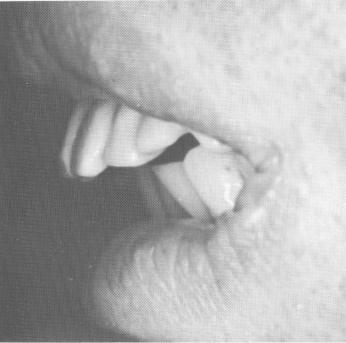

At the next visit, all metal copings were fitted over the prepared teeth (Fig. 15-42). Once again a wax interocclusal record of centric relation was made, and plaster indices were taken to pick up the copings. The laboratory procedures involved soldering the copings together and adding the pontics to fill the edentulous area on the left side of the maxilla. The last pontic was hollowed out and fitted passively over the soft tissues covering the maxillary tuberosity. The two unilateral lower pros-

Fig. 15-41. The master articulated stone casts showing the metal copings in position over the dies. The copings were able to be lined up properly to afford a good final result.

4 Upper and lower master casts show metal coping in position over die